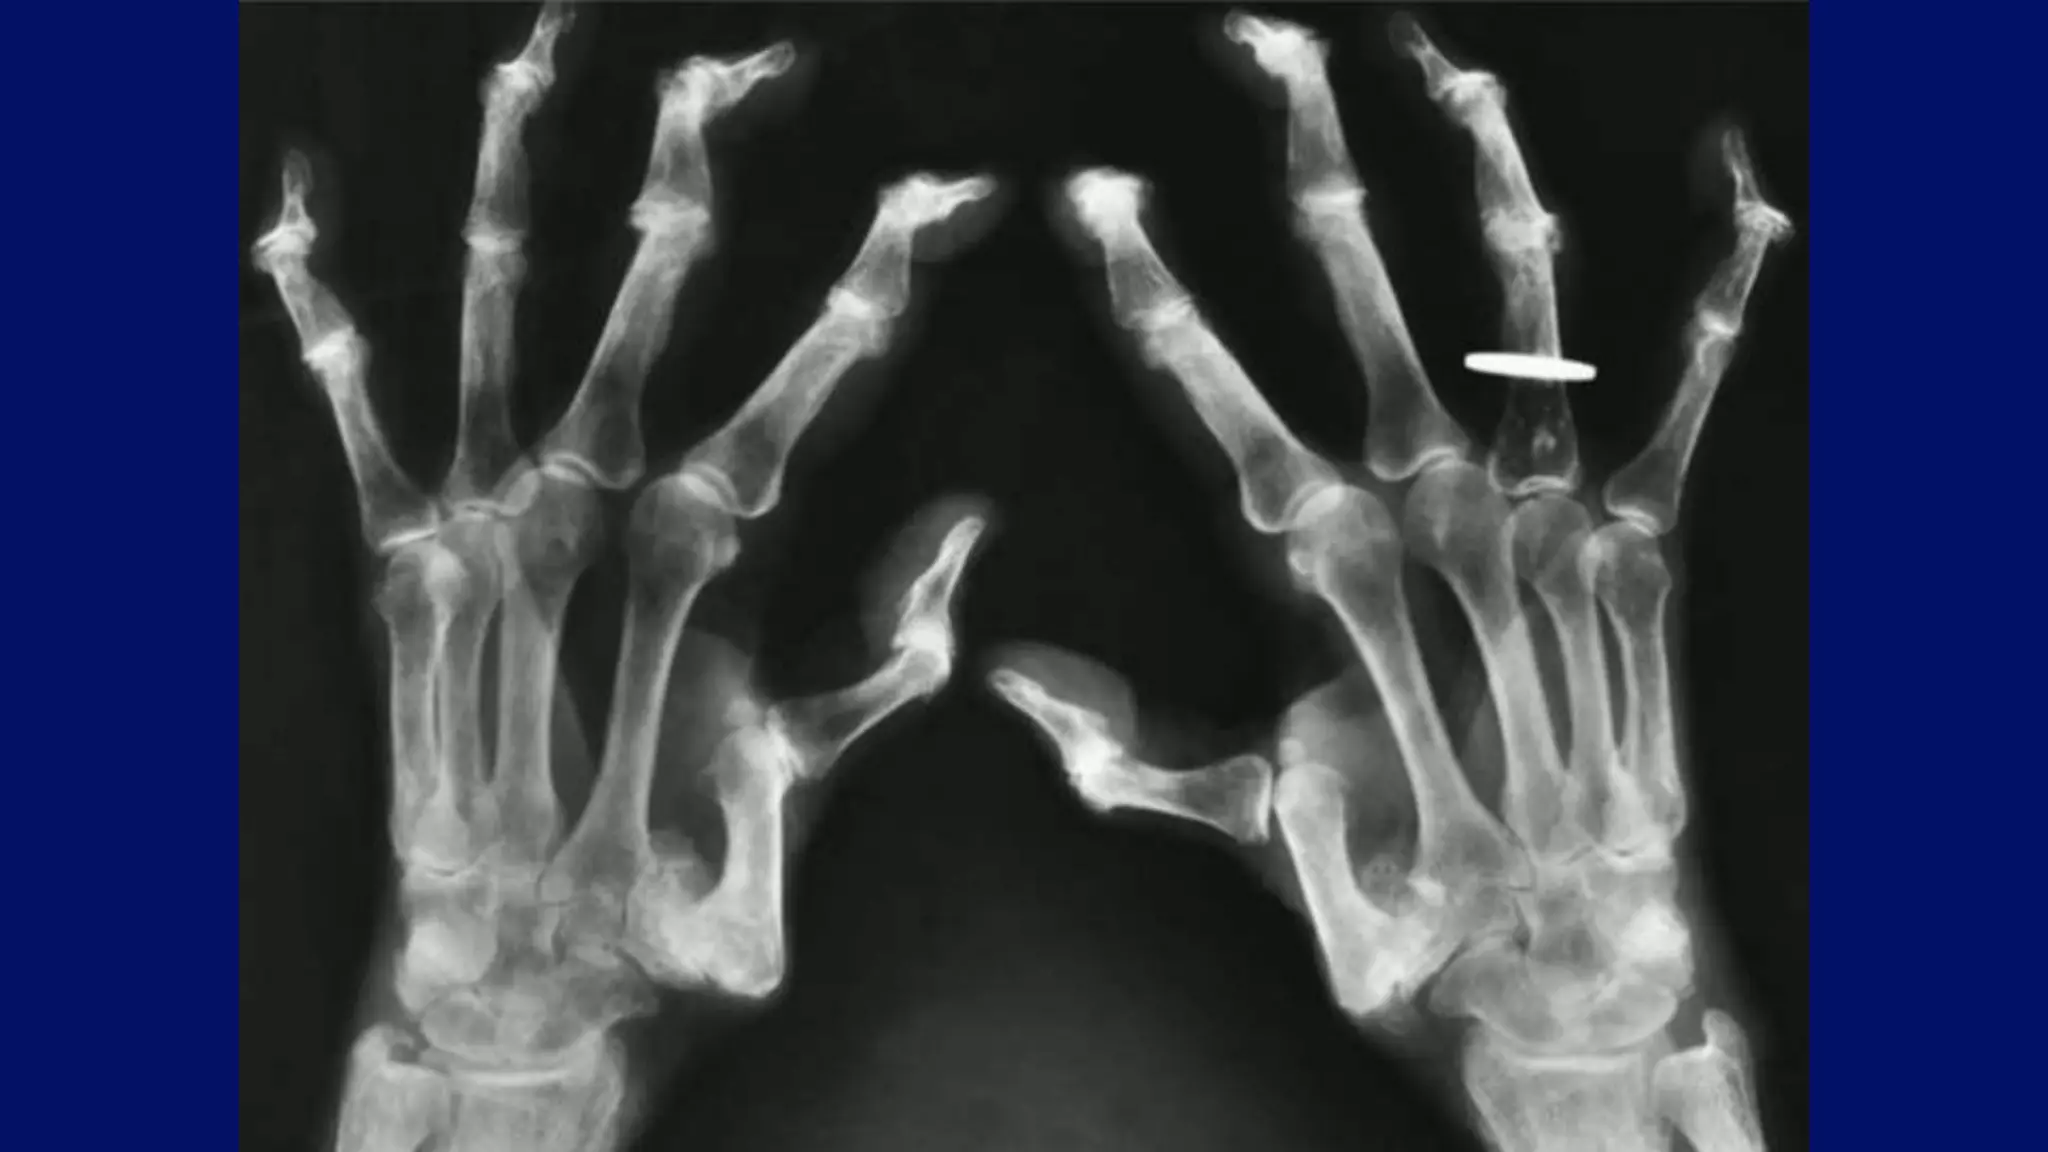

Osteoarthritic features in woman with hemochromatosis

Magnified radiograph demonstrates involvement of the metacarpal heads

Classical hook osteophytes

Advanced Hemochromatosis arthropathy

• #110 thers is relative sparing of IP joint with invovlment of MCP joints Another typical feature of the disease is the presence of hook-like osteophytes generally seen on the radial aspect of the metacarpal heads. Chondrocalcinosis is seen in association with the metacarpal changes, usually best appreciated in the wrist.

• #114 Oblique radiographs of both hands of a 53-year-old woman with hemochromatosis show beak-like osteophytes arising from the heads of the second and third metacarpals on the radial aspect. The interphalangeal, metacarpophalangeal, and carpal articulations are also affected